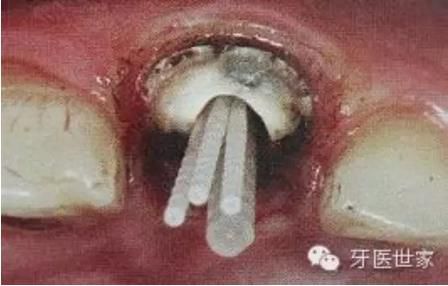

如下圖剩余的組織就過于薄弱,以后也是一個(gè)安全隱患。

一般纖維樁使用數(shù)目要根據(jù)根管的粗細(xì)和牙體缺損范圍來設(shè)計(jì),像牙膠尖根充一樣,在主尖周圍可以放置輔尖。